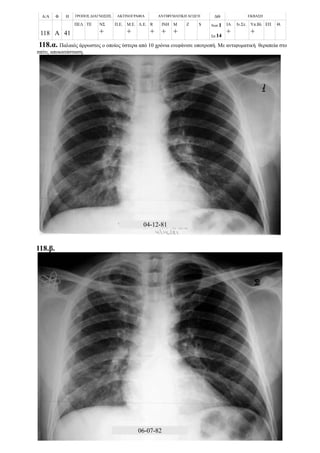

- Περιπτώσεις με επασβαστιωμένη πρωτοπαθή εστία και πρωτοπαθή συμπλέγματα 109

ΦΥΜΑΤΙΩΣΗ

Πρωτοπαθής εστία εν ενεργεία